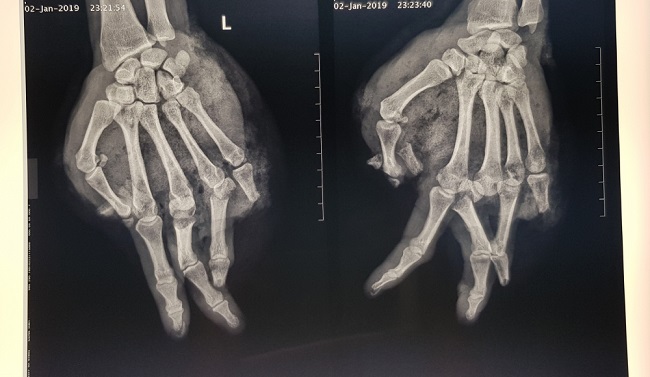

Hình ảnh phim chụp X-quang cho thấy bàn tay của bị bệnh nhân bị chấn thương. Ảnh: Bệnh viện cung cấp. |

Theo bác sĩ Vũ Hữu Trung, bệnh nhân bị tổn thương vết thương phức tạp, dập và lóc da, bầm dập nặng phần mềm bàn tay, dập nát ngón I, V và đốt 2,3 ngón IV; gãy hở nền xương đốt 1 ngón III, IV.